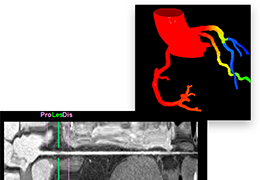

ART-Plan™ Artificial Intelligence Contouring